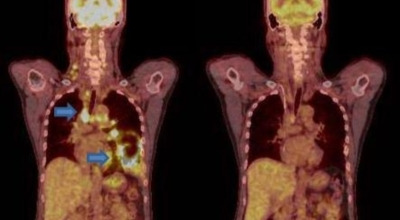

폐암 초기 증상 중 하나로 호흡곤란이 나타날 수 있습니다. 폐암 환자의 약 50%가 숨이 차다고 느낀다고 알려져 있어요. 이는 암 덩어리가 커져 숨이 가빠지는 경우도 있지만, 폐암으로 인한 폐 허탈, 상기도 폐색, 흉막 삼출 등이 호흡곤란을 일으키기도 합니다. 평소와 달리 숨이 차고, 숨을 들이쉬거나 내쉴 때 쌕쌕거리는 소리가 난다면 폐암 초기 증상을 의심해 볼 필요가 있습니다.